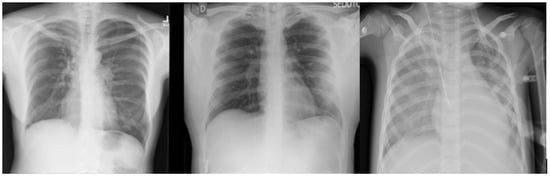

The datasets used in this research were collected from two datasets: the first was from [6], titled “Extensive COVID-19 X-ray and CT Chest Images Dataset” (Available online: https://dx.doi.org/10.17632/8h65ywd2jr.2 (accessed on 25 June 2023 )); the second was from the Kaggle site (Available online: https://www.kaggle.com/paultimothymooney/chest-xray-pneumonia (accessed on 12 June 2023)) that was obtained from [7]. In the collection step, we considered a focus on having a balanced dataset by ensuring that each class comprised almost the same number of X-ray images, each having 5000 X-ray images. Figure 2 shows an example of the collected dataset (X-ray images) with three classes: Normal, COVID-19, and Pneumonia, respectively, from left to right.

For the multi-class classification task used in this research, the dataset consisted of 15,000 X-ray images, labeled with three classes: (1) Normal (which meant that the patient was healthy and was not suffering from any pneumonia type); (2) COVID-19 (which meant that the patient was suffering from pneumonia because of Coronavirus); and (3) Pneumonia (which meant that the patient was suffering from pneumonia because of another type of virus, like SARS). Figure 2 shows an example of the dataset (X-ray images) classes used for multi-class classification tasks: Normal, COVID-19, and Pneumonia, respectively, from left to right.